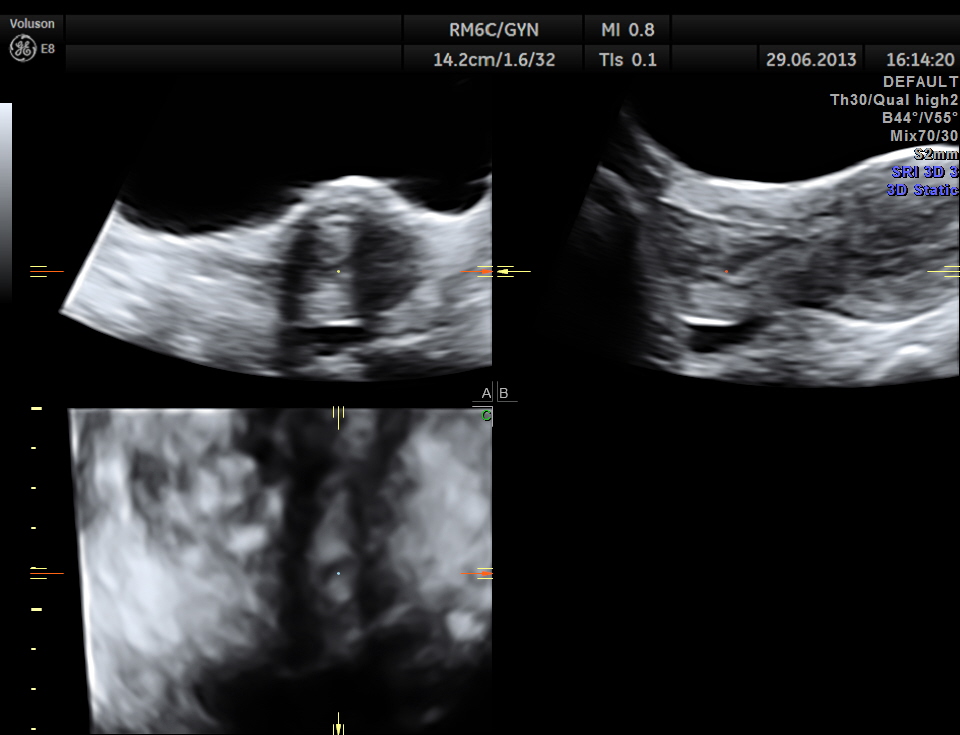

The trans abdominal images are given first. A cervical polyp was seen .

- coronal view ( trans abdominal )

the following images are acquired trans vaginally and the starking difference in clarity can be appreciated.

the multi planar 3 d image shows increased flow in the polyp and the stalk arising from the endometrium

The diagnosis offered was an endometrial polyp with a long stalk situated in the cervix.